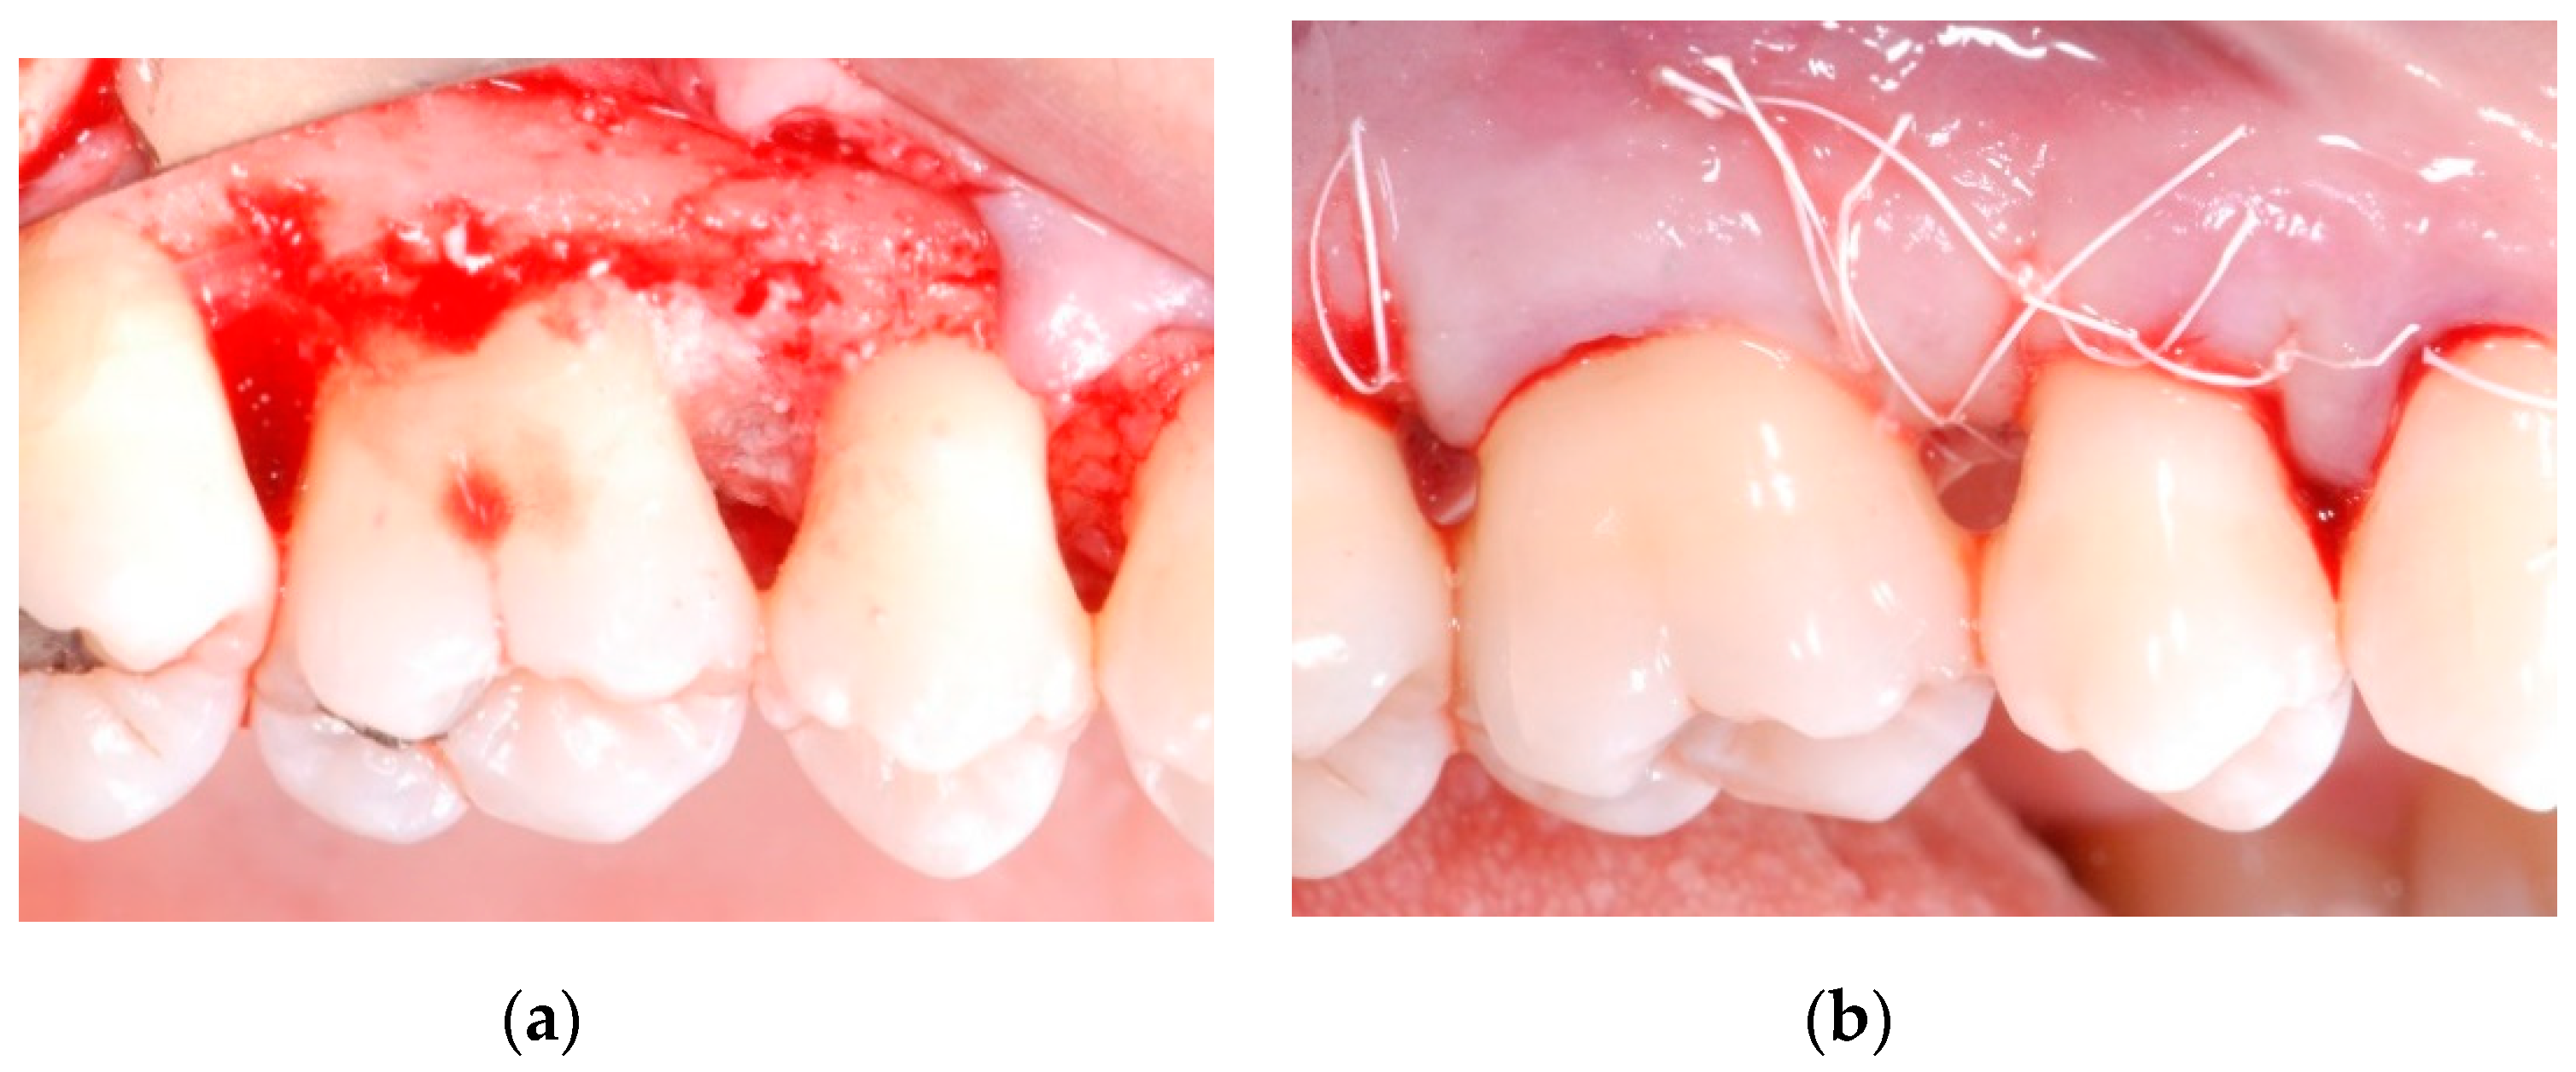

All patients were treated under local anesthesia (articaine 4% with adrenaline 1:100,000). Incisions were performed with a 15b and/or 15c scalpel blade and papillae were preserved in the areas to be regenerated following a previously described technique [25]. Incisions were extended to the adjacent teeth in case multiple sites had to be treated. A full thickness flap was elevated in order to get access to the root and the periodontal intrabony defect (Figure 1a,b); a combination of ultrasonic device and manual curettes was used to debride the area and to remove calculus and inflammatory tissue. The intrabony component of the defect was then filled by a composite graft consisting of nanohydroxyapatite powder (NHA) with crystals varying in size between 70 and 100 nm (Neo Active Apatite, Ghimas, Casalecchio di Reno, Italy) mixed with poly lactic-co-glycolic acid (PLGA) (Fisiograft Gel, Ghimas, Casalecchio di Reno, Italy) (Figure 2a). The mix ratio was 1:1 by volume. The buccal flap was then slightly released by longitudinal periosteal incision and 5.0 monofilament sutures were used to obtain primary soft tissue closure with vertical mattress sutures (Figure 2b).

Figure 2.

(a) After accurate debridement, the intrabony component of the defect was filled by a composite graft consisting in nanohydroxyapatite powder mixed with poly lactic-co-glycolic acid; (b) The buccal flap was then slightly released by longitudinal periosteal incision and closed with vertical mattress sutures.